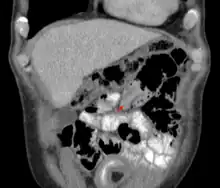

Uma intussuscepção é uma condição médica na qual uma parte do intestino se invagina (se dobra) por sobre outra seção do intestino, semelhante à maneira como as partes de um telescópio se retrai sobre a outra parte.[1] Muitas vezes pode resultar em obstrução. Poucas intussuscepções reduzem espontaneamente, mas, se não tratadas, a maioria levará a infarto intestinal, perfuração, peritonite e óbito.[2]

Um raio-x de abdômen pode ser indicado para verificar obstrução intestinal ou gás intraperitoneal livre. A última constatação implica que a perfuração intestinal já ocorreu. Algumas instituições utilizam enema de ar para o diagnóstico, e o mesmo procedimento pode ser utilizado para tratamento.[5]